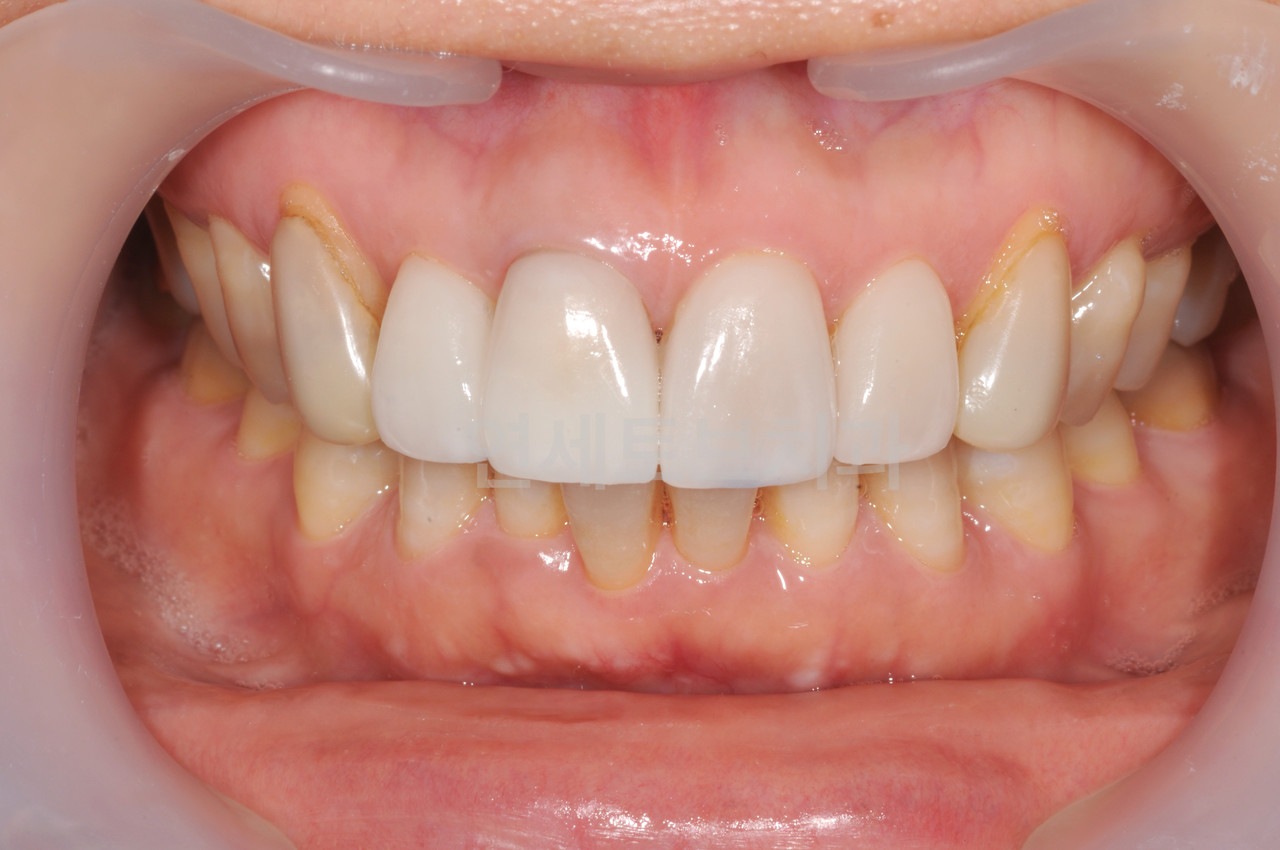

02

티 나지 않는 자연스러움,

잇몸 변색 걱정 없는 올세라믹 크라운

올세라믹은 치아의 모든 면을 일정하게 깎아낸 후, 100% 세라믹을 이용해 치아전체를 감싸주는 심미치료입니다.

시술이 간편하고 원하는 치아의 모양, 색상, 형태로 맞춤 제작을 할 수 있으며, 심미성과 함께 내구성이 뛰어나 저작력이 우수합니다.

자연치아와 거의 흡사한 색상과 투명도

인체 무해한 재료로 잇몸 조직과 높은 친화성

금속 성분이 없어 잇몸 변색 걱정 감소

전체 얼굴 골격과 이미지를 고려한 디자인

올세라믹은 강도가 높은 세라믹만으로 치아의 투명도를 재현할 수 있어 빛이 투과되어 자연스러우며 잇몸 주변에 검은 그림자가 생기지 않습니다.

라미네이트 치료를 할 수 없거나 신경치료를 한 치아의 경우, 치아의 마모나 파절 정도가 크거나 강한 힘을 필요로 하는 부위에 시술합니다.

Before

올세라믹 크라운 시술 전

After

올세라믹 크라운 시술 후

올세라믹은 치아의 모든 면을 일정하게 깎아낸 후,

100% 세라믹을 이용해 치아전체를 감싸주는 심미치료입니다.

자연치아와 거의 흡사한

색상과 투명도

인체에 무해한 재료로

잇몸 조직과의 높은 친화성

금속 성분이 없어

잇몸 변색 걱정 감소

전체적인 얼굴 골격과

이미지를 고려한 디자인

올세라믹은 강도가 높은 세라믹만으로 치아의 투명도를 재현할 수 있어

빛이 투과되어 자연스러우며 잇몸 주변에 검은 그림자가 생기지 않습니다.

라미네이트 치료를 할 수 없거나 신경치료를 한 치아의 경우,

치아의 마모나 파절 정도가 크거나 강한 힘을 필요로 하는 부위에 시술합니다.